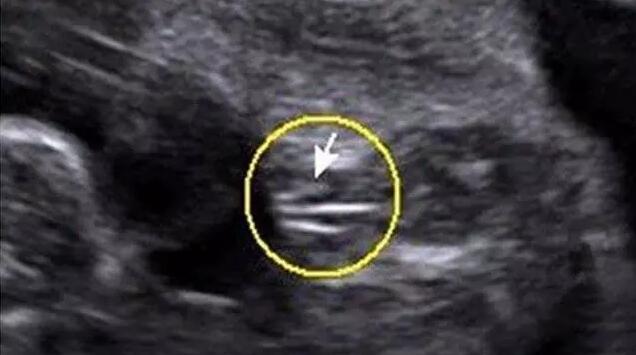

女宝B超图的特征是“三条白线”,当然最好的角度还是从下方来看。如果没有看到三条白线,那么就瞪大眼睛看双腿之间突出的部分,如果特征为两边鼓中间凹,那就基本是女宝了。如下图所示。

三条白线